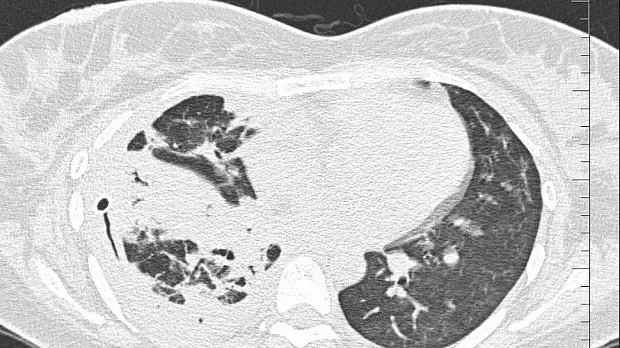

08.06.2020 проведена повторная установка блокатора в промежуточный бронх (блокатор Medlung №13) с хорошим клиническим эффектом (сброс воздуха по плевральному дренажу прекратился через 8 часов после вмешательства). Подтверждено данными Р-КТ органов грудной клетки.